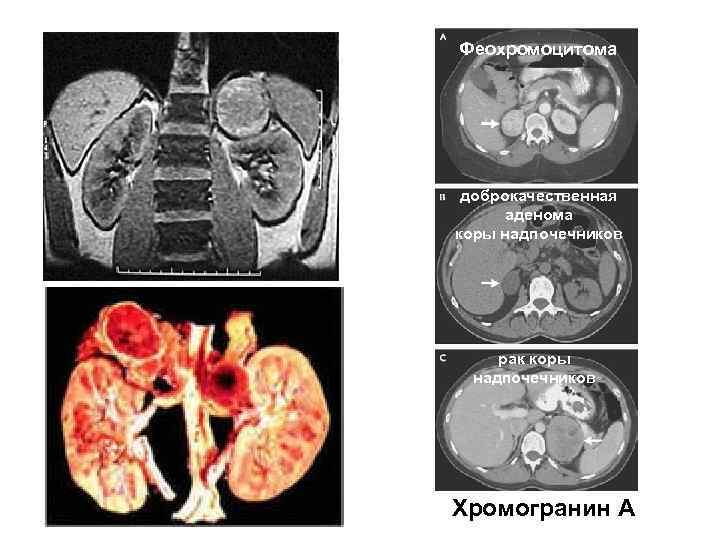

Феохромоцитома доброкачественная аденома коры надпочечников рак коры надпочечников Хромогранин А

Феохромоцитома доброкачественная аденома коры надпочечников рак коры надпочечников Хромогранин А